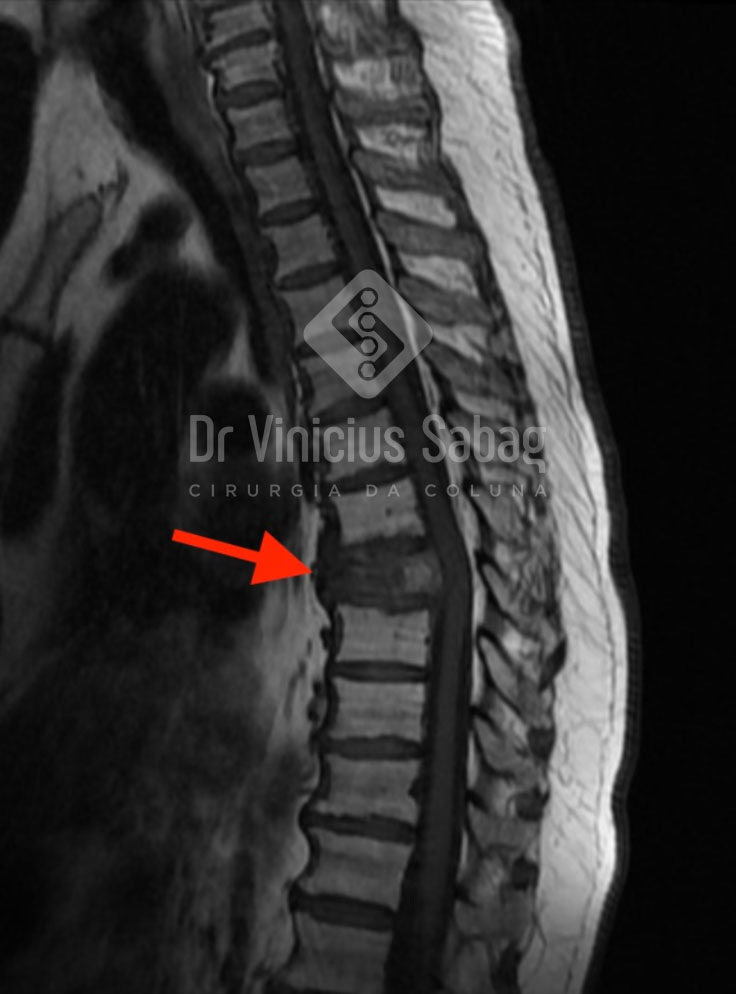

Ressonância magnética evidenciando lesão metastática na coluna vertebral.

A metástase óssea acontece quando as células cancerígenas da próstata se deslocam pela corrente sanguínea e se instalam em ossos — geralmente na coluna vertebral, quadril, fêmur e costelas.

Essas células comprometem a estrutura óssea, causando dor intensa, inflamações e até fraturas espontâneas.

- Ressonância magnética ou tomografia computadorizada – para avaliar a extensão da lesão óssea;